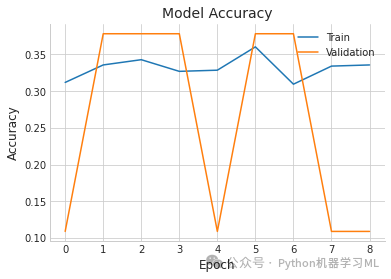

阶段九:模型评估与可视化

plt.plot(history.history['accuracy'], label='Train') # 绘制训练集准确率曲线

plt.plot(history.history['val_accuracy'], label='Validation') # 绘制验证集准确率曲线

plt.title('Model Accuracy') # 设置图表标题

plt.ylabel('Accuracy') # 设置y轴标签

plt.xlabel('Epoch') # 设置x轴标签

plt.legend() # 显示图例

plt.show() # 显示图表

9/9 [==============================] - 6s 253ms/step precision recall f1-score support

0 0.00 0.00 0.00 30 1 0.00 0.00 0.00 141 2 0.38 1.00 0.55 104

accuracy 0.38 275 macro avg 0.13 0.33 0.18 275weighted avg 0.14 0.38 0.21 275

[[ 0 0 30] [ 0 0 141] [ 0 0 104]]